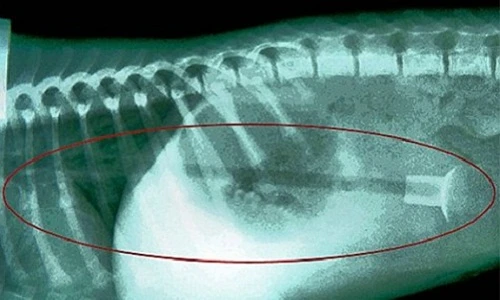

Một con chó con giống Labrador 6 tháng tuổi được phát hiện nuốt chửng 13 viên đá vào trong người sau khi chủ của nó nhận thấy con vật không ăn cơm và đưa đến bác sĩ thú y. Kết quả chẩn đoán hình ảnh cho thấy các viên đá bắt đầu đi vào ruột.

Ozzie, một con chó 7 tháng tuổi ở Cubbington, Anh đánh nhau giành một món đồ chơi bằng nhựa với một con chó khác. Nhận thấy mình sắp thua nên con chó đã nuốt chửng món đồ chơi vào bụng. Nó phải trải qua phẫu thuật khẩn cấp mới trở lại bình thường.